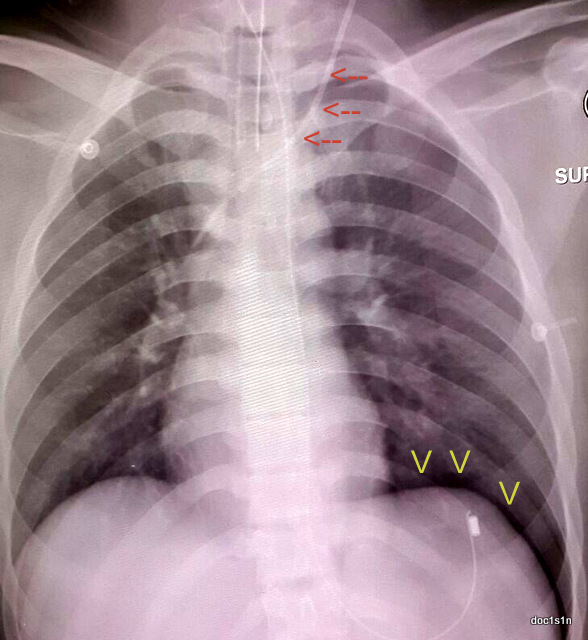

i was doing an invasive procedure called central venous cannulation, essentially inserting a plastic tube (red arrows) into a vein lying within the chest, when i accidentally punctured the left lung.

this resulted in an abnormal collection of air (yellow arrows) called a pneumothorax in the space between the left lung and the diaphragm. it was potentially life-threatening and was managed by inserting another tube into the chest that provides an escape route for the air pocket into a bottle.